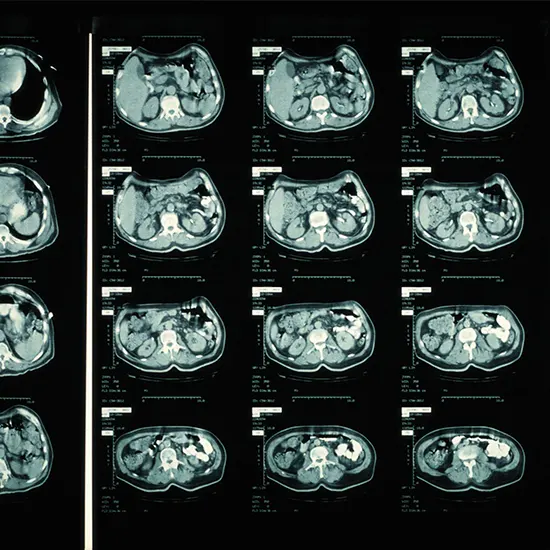

The length of a CT (computed tomography) check exam can change depending on the particular type of scan being performed, the body portion being scanned, check filtered and the patient's condition. For the most part, a CT filter can take anyplace from a couple of minutes to 30 minutes.

For case, a standard head CT filter more often than not takes around 5-10 minutes, whereas a chest or stomach CT filter may take around 15-20 minutes. More complex checks, such as a CT angiography or a CT enterography, can take longer, up to 30 minutes or more.